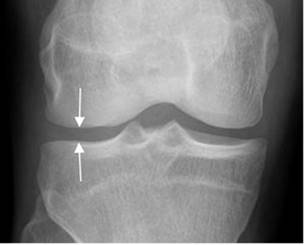

Fig 17. Hemartrosis.

A: Rx AP. Fracturas no desplazadas, ni deprimidas en los platillos tibiales.

B: Rx lateral con rayo horizontal. Nivel grasa/líquido en la región suprapatelar, por hemartrosis.